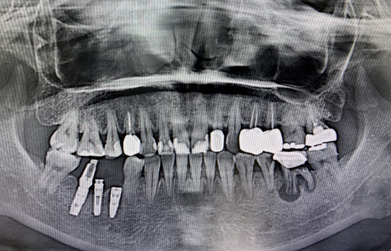

一口潔白整齊的牙齒,可以增加你的自信,讓你盡情展露笑容。但是很多人因為各種原因,從而缺失了自己的牙齒。嚴重影響的形象美觀及正常咀嚼功能。不過現(xiàn)在種植牙是非常熱門的項目,效果也是很不錯的。 種植